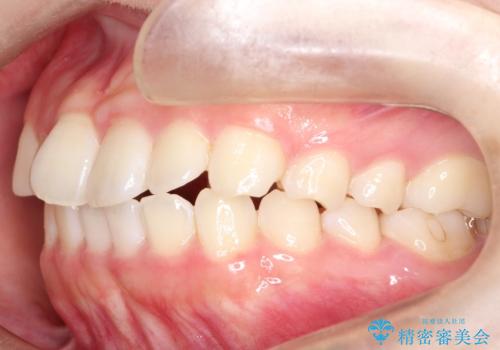

【インビザライン】前歯の凸凹をなおしたい

- 前歯のガタガタを主訴に来院されました。

インビザラインで綺麗な歯並びになり、患者さんには大変満足していただきました。